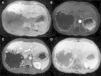

HHs are suspected when ultrasonography shows nodules with homogeneous hyperechogenicity, but additional imaging tests, usually triphasic computed tomography (TCT) or magnetic resonance imaging (MRI), are required to confirm the diagnosis due to the lack of specificity of ultrasonographic findings. TCT typically reveals progressive enhancement during the arterial phase in a centripetal fashion. MRI shows a low signal intensity on T1-weighted images, high signal intensity on T2-weighted sequences, and an inward enhancement after gadolinium administration can be seen.14 Tc-99m-labeled red blood cell single emission photon computed tomography may be helpful when there is diagnostic uncertainty; it has sensitivity, specificity and accuracy of 97%, 83%, and 96%, respectively.15 Positron emission tomography is useful to differentiate heterogeneous HH from angiosarcomas.16 The differential diagnosis includes angiomatosis, metastases, hematic cyst, hepatic peliosis, and hepatocellular carcinoma, among others.

MethodsWe performed a retrospective analysis of patients with HH at our hospital within the time frame of January 1, 1990 and November 31, 2008. We made an electronic search regarding outpatient and inpatient hospital records looking for the diagnosis of hemangioma and/or benign hepatic tumor, which corresponded to the D 18.0 and D 13.4 categories of the CIE 10, respectively. We included all patients with GHH and HH, and diagnosis was based on the presence of conclusive imaging findings on TCT or MRI (peripheral nodular enhancement in the early phase followed by centripetal enhancement during the late phase) (figs. 1-4) or on the histopathology report. Medical records were reviewed for each patient to obtain demographic, clinical, radiological, and laboratory information, evolution, and treatment; if surgery was performed, data regarding the type of surgery, duration, complications, and transfusion requirements were recorded. Pain due to HH was defined as persistent pain in the upper right abdomen that could not be better explained by an alternative diagnosis, including irritable bowel syndrome.

Triphasic Computed TomographyA 16 or a 64-slice multidetector CT (Somatom, Sensation 16 or 64; Siemens Munich, Germany) was used; images were obtained with a section thickness of 3-5mm and a reconstruction interval of 2-2.5mm. All cases were analyzed on a workstation with the capacity to produce coronal reformatted images. All patients received both intravenous and oral contrast. For intravenous contrast, 120ml of Conray (Mallinckrodt Baker Inc., St Louis Missouri, USA) was given 45 s prior to performing the scan; for oral contrast, 40ml of Ioditrast M60 (Justesa Imagen Mexicana) were diluted in 1,000ml of water and given to all patients orally one hour prior to computed tomography. All TCT images were analyzed by at least 2 certified radiologists.

Magnetic resonance imagingMagnetic resonance imaging (MRI) was performed on a 1.5 T system (Signa Excite HD, GE Healthcare, Milwaukee, USA), using a variety of software upgrades that evolved during the study period. Standard liver imaging sequences included T1-weighted In-phase and Opposed-phase gradient echo and T2-weighted fast spin echo sequences. T1-weighted imaging was repeated after contrast material administration during hepatic arterial (19-25 s), portal (40-45 s), venous (60-65 s) and delayed (3-5min) phases. Patients received Gadopentate Dimeglumine (Gd-DTPA [Magnevist, Bayer Schering Pharma]) at a mean dose of 0.1 mmol/kg of body weight, a unique bolus at a 1.5 - 2ml/s rate, followed by a saline flush (mean volume 20ml).